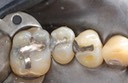

Kyle Chock #18 pre-op